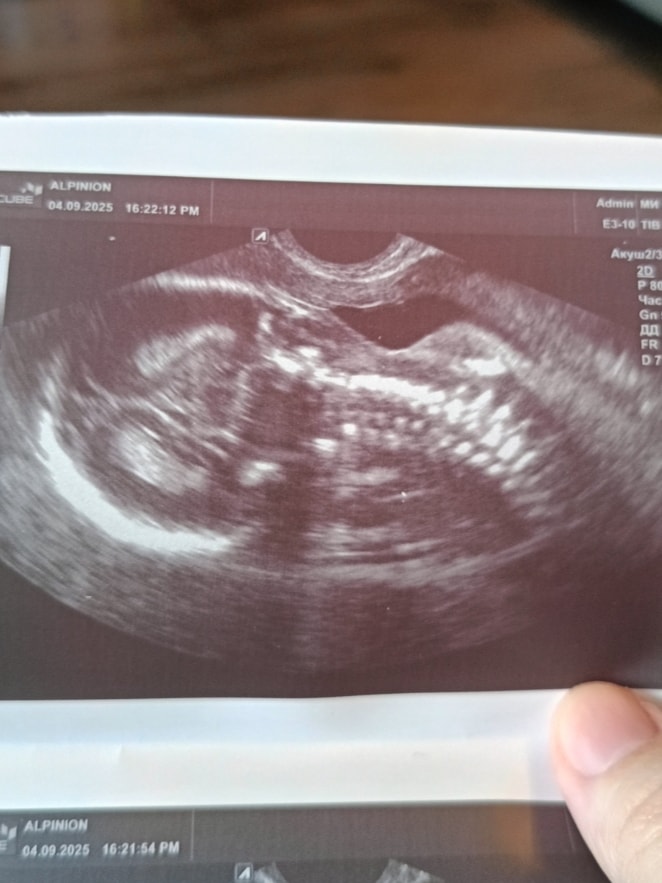

Анализы, скринингиВ этот раз пошла на платное узи, тк в бесплатной поликлинике на 1 скрининге ждала 4,5ч(!) в очереди. Сходила в Инвитро. Понравилось, что не нужно было ждать, распечатали фото (ребёнок лежит головой вниз, отвернувшись, поэтому вид только сзади). Подтвердили девочку (до этого после 1 скрининга сдавала кровь в Инвитро, тогда пришла девочка), сказали, что все в норме. Но мне ни разу не повернули монитор, хотя у прошлого узиста (он только до 10 недель) мне все показывали. Также не написали вес плода, хотя у них написано, что должны проверять. Шейка матки укоротилась с 34мм (мерили в 12,3, в 16,4) до 31мм (19,3). По узи головка на 18,3 недель, ручки на 19,0, живот на 19,0, а бедра на 19,5. Впечатления неоднозначные, врач во время приёма говорила на посторонние темы по телефону, ничего не показала, вес не указала (хотя для меня это была важная информация). Думаю в 22-24 недели пойти повторно на узи, только не к ней, заодно проверю шейку, сейчас ее лучше понаблюдать. На прием только 15 числа, до этого 11 пойду сдавать мочу и кровь на анализы.